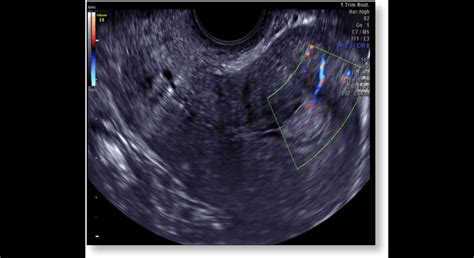

Diagnostika dvojrohej maternice zvyčajne začína dôkladnou anamnézou a fyzikálnym vyšetrením. Kľúčovú úlohu zohráva zobrazovacia diagnostika:

- Panvový ultrazvuk: Je často prvým zobrazovacím vyšetrením, ktoré môže naznačiť anomáliu maternice.